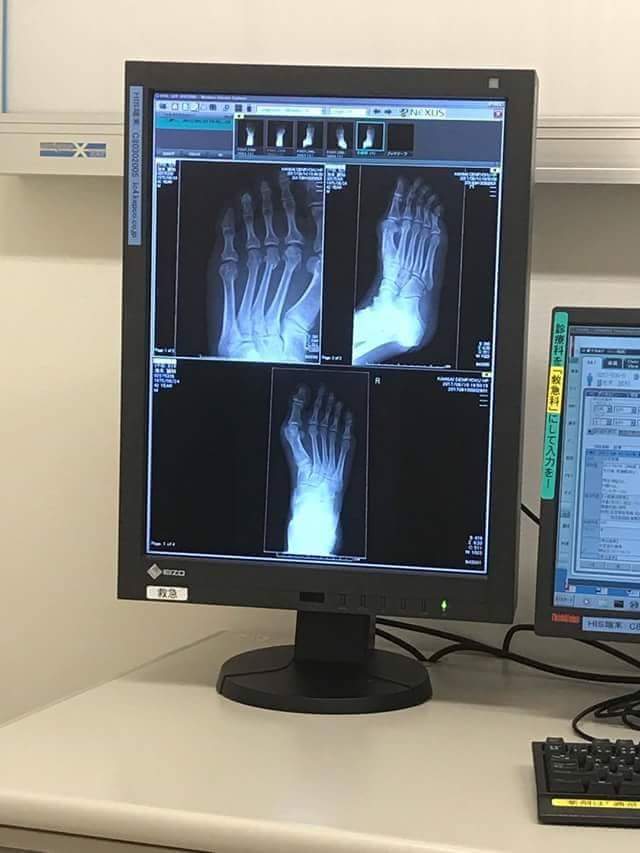

22日の試合のメインイベントに出場予定をしていた『 池本誠知 』選手が、9日に開催された彼の経営する『 総合格闘技スタジオ STYLE 』さんの創立10周年記念のパーティの席上で、来賓のお客様の前で披露したエキジビションマッチに於いて、左足の骨を粉砕骨折してしまい、試合の履行が不可能となってしまいました。

メインイベントの他にも、自分自身の出来る限りのマッチメイクが今回は出来たとの確信がありましたが、10日の深夜に骨折との連絡が入り、既に松葉杖を付かないと歩行出来ない状況でしたので、一昨日から参戦選手に個別に状況をお話しし、今大会の延期への承諾を戴いた次第です。

池本選手とは、昨晩も遅くまで話をしましたが、明日再度病院に診てもらい、手術かどうか?手術なら入院ということにもなるそうで、そのあたりの検診をするそうです。